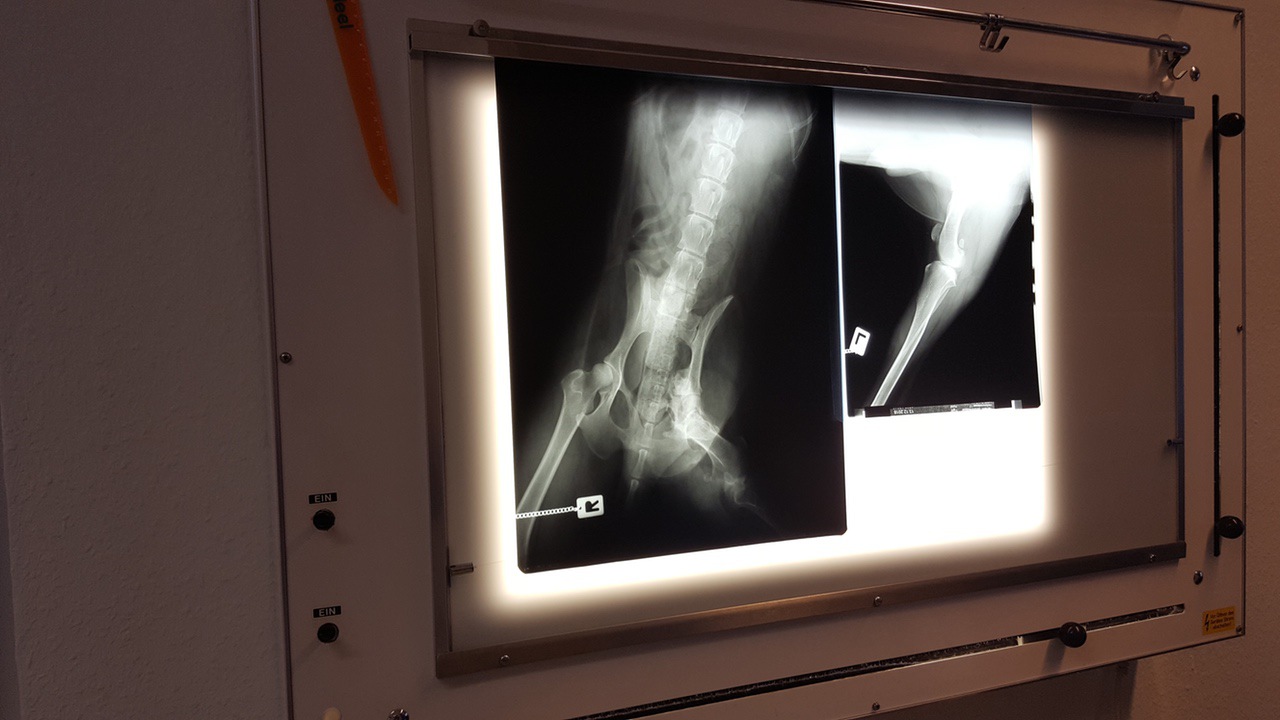

Also reiste große Hoffnung mit zum Termin. Leider gab es stattdessen dann große Enttäuschung. Weder bei Filou noch bei Fight kann man etwas machen. Die Verletzungen sind einfach zu alt. Es gäbe die Möglichkeit, bei beiden das betroffene Bein zu amputieren. Davon riet Dr. Köhle jedoch ab. Filou und Fight haben keine Schmerzen. Sie benutzen das kaputte Bein jeweils aber noch zum Stützen beim Laufen. Eine Amputation wäre also ein Eingriff, der zu Komplikationen führen kann, ohne dass es Gewinn bringt.